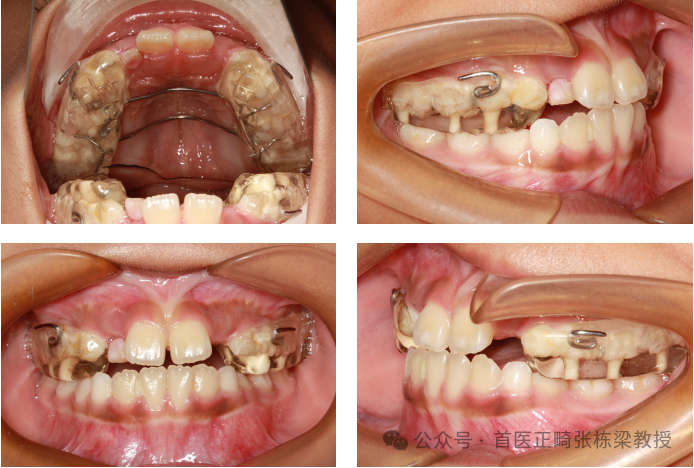

那么如果说孩子不是骨骼的问题,是由于牙齿的倾斜造成的地包天,大概率都是上牙的舌倾,如果是这样的情况,可以选择使用活动矫治器,我们叫颌垫双曲推簧矫治器。

当然也可以用其他好的方法,比如说我可以做透明矫治器挂三类牵引,这也是很快速的解决地包天问题的方法。

但是如果是骨性地包天的问题,那我们就需要使用RME+前方牵引,促进上颌骨往外拽。

一般我们在做前方牵引的时候,我们常规的需要的牙齿是3、4、5,但是有些孩子来的时候牙齿就已经坏了,这个非常可惜做不了。

要么就重新治好了然后你再做,要么治也治不好都剩残根了或者马上就要掉了,目前对于这种坏牙的话,我可能更多的是采用透明的压模矫治器,挂三类牵引的皮筋。